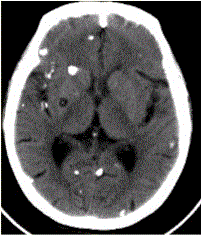

问题 患者男,45岁。头痛、癫痫10余年。查体:无发热,双侧肢体肌力正常。脑电图示双侧额颞叶棘波放电。CT表现如下图。 头颅CT检查中,描述不正确的是

选项 A.囊虫存活时(活囊虫),周围脑实质有显著水肿 B.囊虫存活时,周围脑实质没有水肿 C.囊虫死亡后(死囊虫),周围脑实质有显著水肿 D.囊虫死亡后,周围脑实质不再有水肿 E.无论囊虫存活与否,周围均有水肿 F.囊虫钙化沿血管分布 G.囊虫内可见头节

答案 ADEF